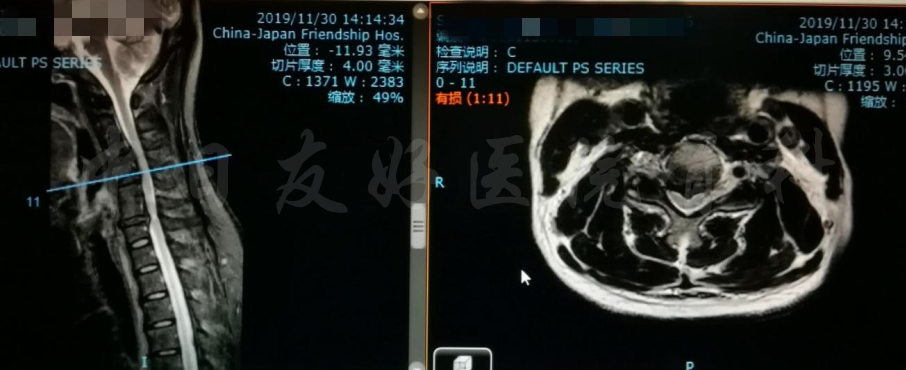

MRI

MRI颈4-5(左)、颈5-6(中)颈6-7(右)

矢状位MRI

轴位MRI:腰3-4(左)、腰4-5(中)、腰5骶1(右)

2019年11月30日 颈椎MRI提示:颈3/4颈4/5颈6/7椎间盘突出,椎管狭窄;颈5-6水平脊髓异常信号,变性可能。

颈椎MRI

颈椎MRI

颈椎各节段MRI(上下滑动)